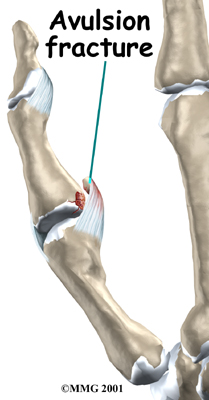

Sometimes the ligament itself will not tear but instead pulls a small piece of bone off the base of the thumb where it attaches. This is called an avulsion fracture. This can also lead to an unstable thumb joint if the fracture does not heal correctly.

Avulsion Fracture